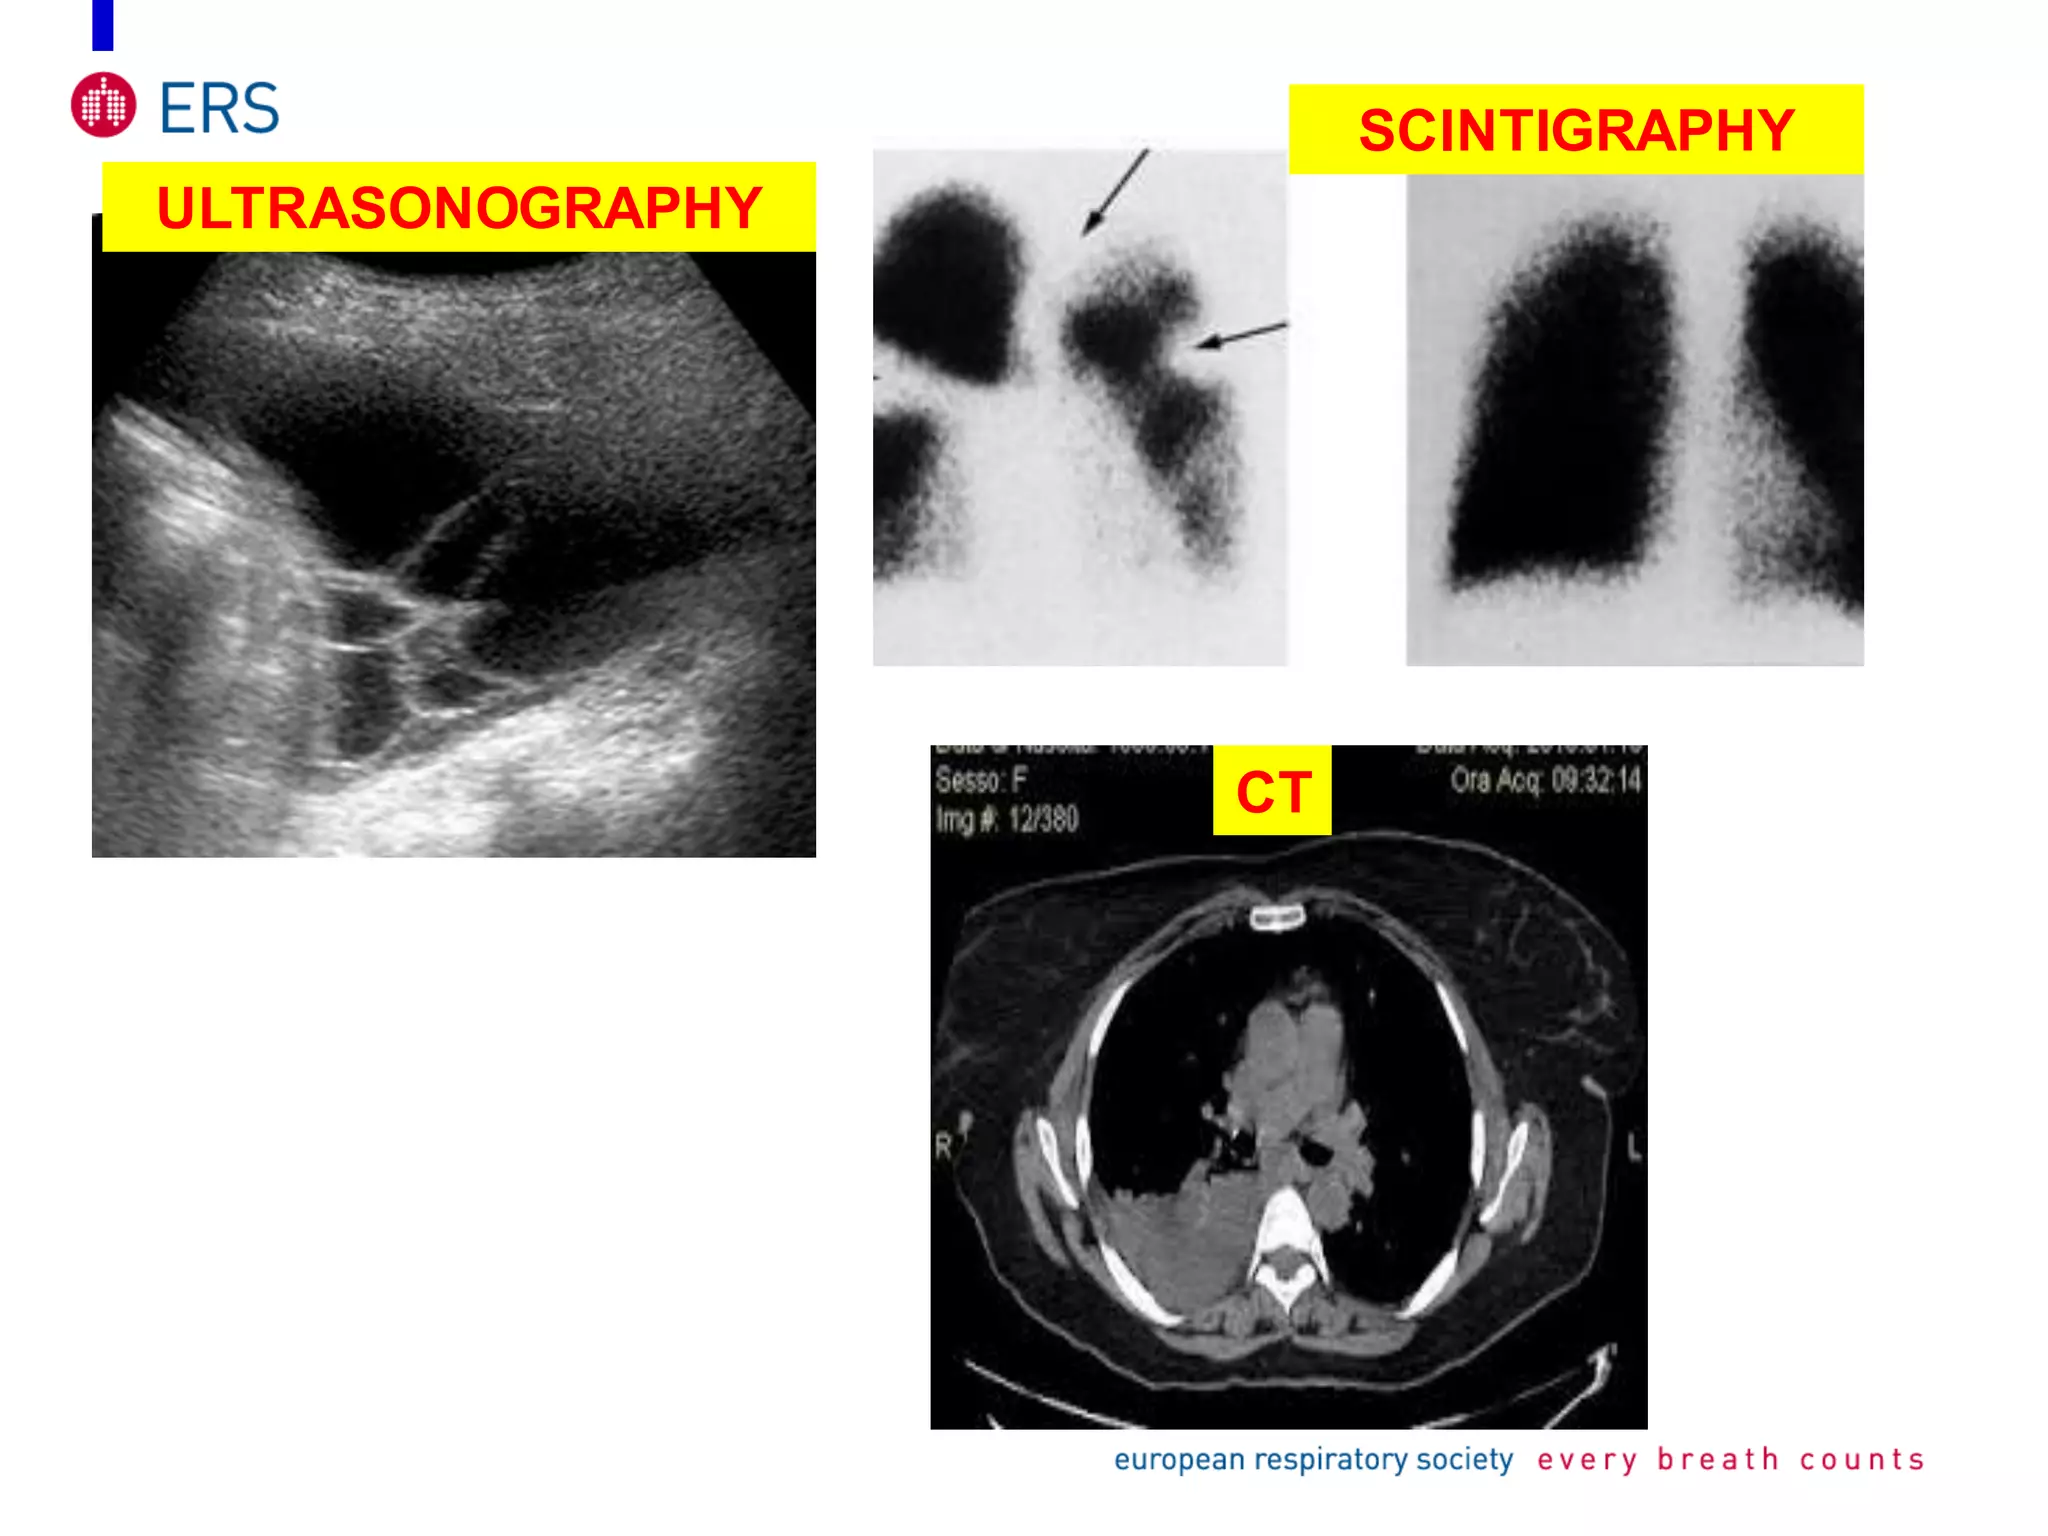

X RAY

ULTRASONOGRAPHY

CT

SCINTIGRAPHY